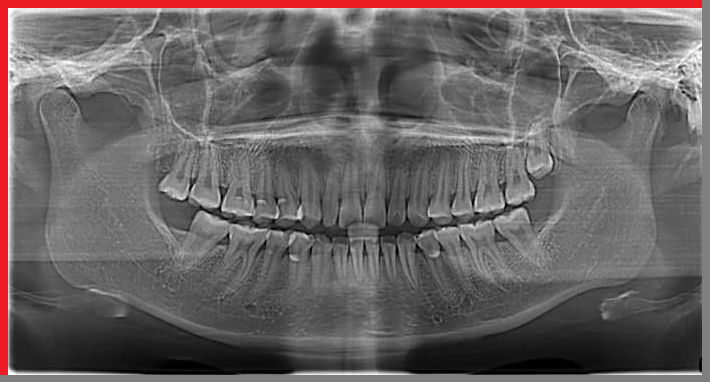

Để thực hiện niềng răng các bác sĩ phải lên phác đồ điều trị cụ thể đối với từng trường hợp. Để có thể chẩn đoán chính xác và lên kế hoạch điều trị hợp lý, bác sĩ phải hiểu rõ đặc điểm xương hàm, trục răng, mức độ lệch lạc của răng và độ cứng chắc của răng như thế nào... Do vậy chụp Xquang trước khi niềng răng là việc rất cần thiết. Thông qua những hình ảnh thu được từ việc chụp phim Xquang khi niềng răng kết hợp với hình ảnh thăm khám khoang miệng, ngoài mặt, lấy dấu mẫu hàm, bác sĩ mới có thể đưa ra được những nhận định và phán đoán chính xác về tình trạng răng, hướng dịch chuyển của răng sau khi niềng và lên phác đồ cụ thể cho từng trường hợp.

Niềng răng trong chỉnh nha là một điều trị trong khoảng thời gian dài, từ 2 - 3 năm, điều này có thể khiến bác sĩ không thể nhớ hết được những điều trị của mình cũng có thể bệnh nhân sẽ quên đi hàm răng trước khi niềng của bản thân. Vì vậy việc chụp Xquang sẽ cho phép bác sĩ và bệnh nhân có cái nhìn toàn diện và chính xác hơn trong quá trình niềng răng.

Bên cạnh đó, chụp phim Xquang là một trong những cách lưu trữ thông tin về tình trạng răng và xương hàm của bệnh nhân tốt nhất, dựa vào các hình ảnh trên phim qua các lần chụp bác sĩ và bệnh nhân có thể thấy được sự di chuyển của răng cũng như hiệu quả quá trình điều trị chỉnh nha.